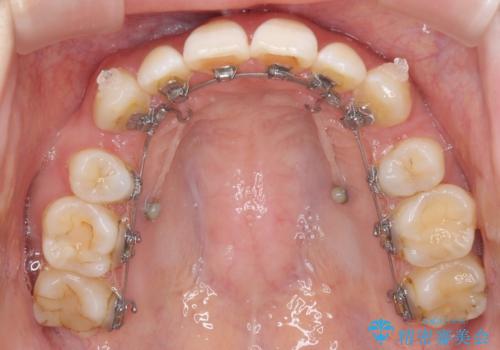

- ハーフリンガル

- 口元の突出感を気にして来院された患者様です。

上下左右の第一小臼歯4本を抜歯して口元を下げる治療計画としました。

裏側矯正特有の抜歯スペースに前後の歯が倒れ込む状態が長く続き、改善に長期間を要しました。